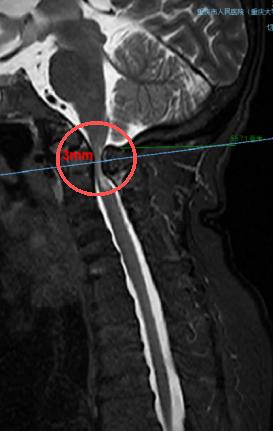

術前,頸椎MRI顯示,患者脊髓嚴重受壓(圓圈處)。重慶市人民醫院(重慶大學附屬人民醫院)供圖